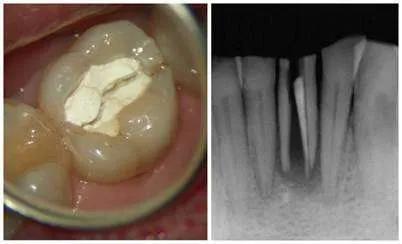

5、牙劈裂

这是很严重的一种情况,可能导致牙被拔掉,牙齿裂开以后除非把松动部分牙齿拔除,否则真的咬不了东西